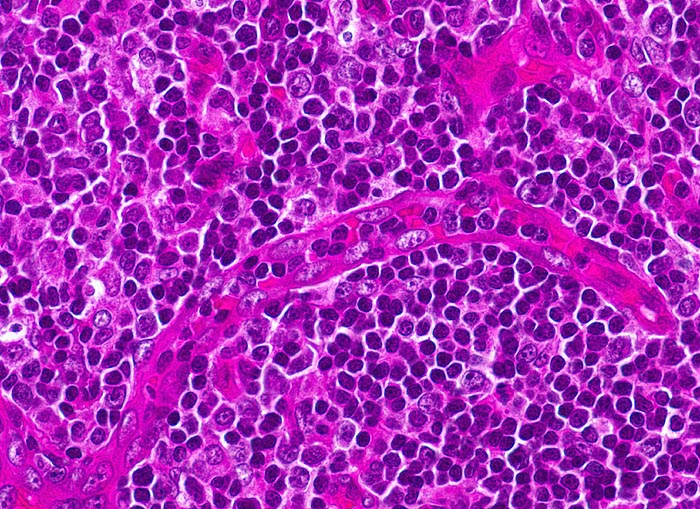

infektiöse Mononukleose

Tonsille

Hochendotheliale postkapilläre Venole mit gesteigerter Lymphozyten-Rezirkulation. Daneben buntes Zellbild: kleine Lymphozyten, stimulierte Lymphozyten, Immunoblasten mit zentralem Nukleolus und Plasmazellen mit paranukleärer Aufhellung des Zytoplasmas.

Tonsillektomie bei einem Studenten mit Angina, Lymphknotenschwellungen und einer Lymphozytose im Blut.

400